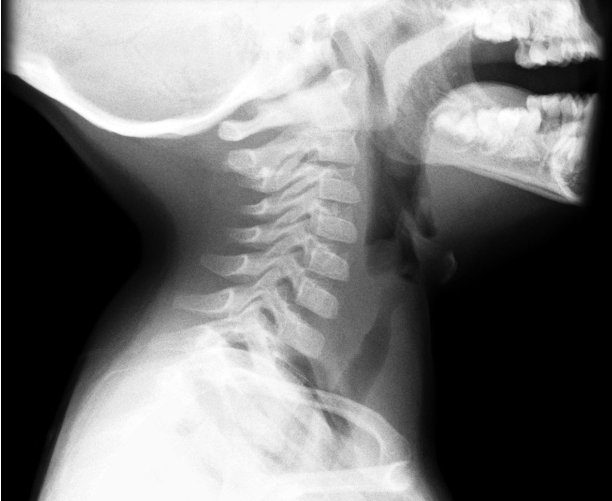

Xray findings in epiglottitis:

A

“Thumb sign”